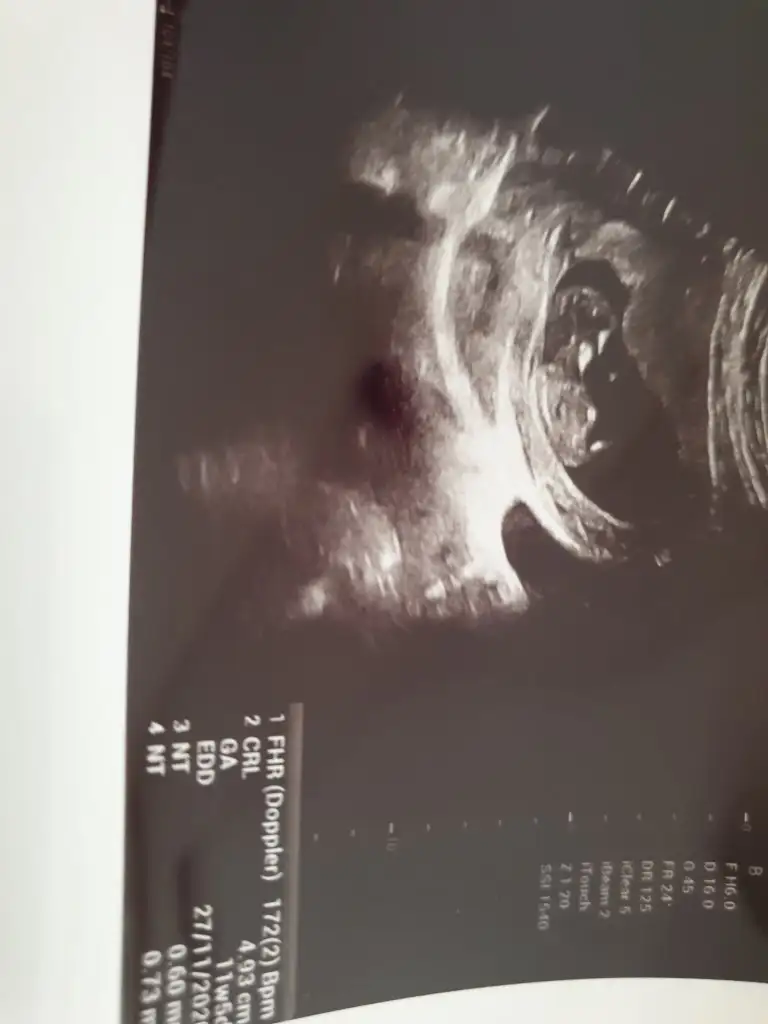

Canım ultrason fotosu varsa atar misin nub una bakalım

Aaa sende anlıyor musun canım ben yüklememiştim dur şimdi yükleyimde bana da bir tahminde bulunan bakalım kızlar heyecan yaptım

Ben burda çok okudum öyle şeyleri. Eğer görebilirsem yorumda bulunabilirim canım. Yolla gelsin